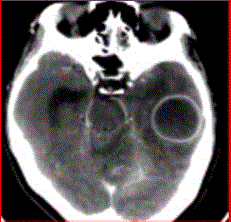

问题 患者女,26岁,头痛、低热10d余,既往有左侧慢性中耳炎病史。CT表现如下图。 初步诊断为

选项 A.脑脓肿 B.胶质瘤 C.脑血肿 D.脑梗死 E.脑囊虫

答案 A